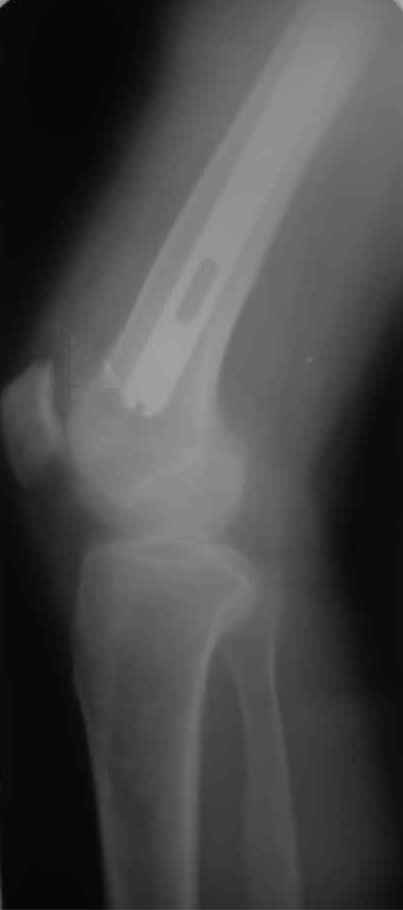

А нельзя ли увидеть и профиль бедра на всем протяжении, т.е. и весь протез, и весь стержень? И фас бы с коленом.

новые снимки